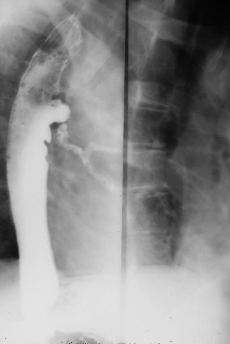

Hernie hiatală

Hernie hiatală prin alunecare

Hernie hiatală prin rostogolire

Hernie hiatală - brahiesofag